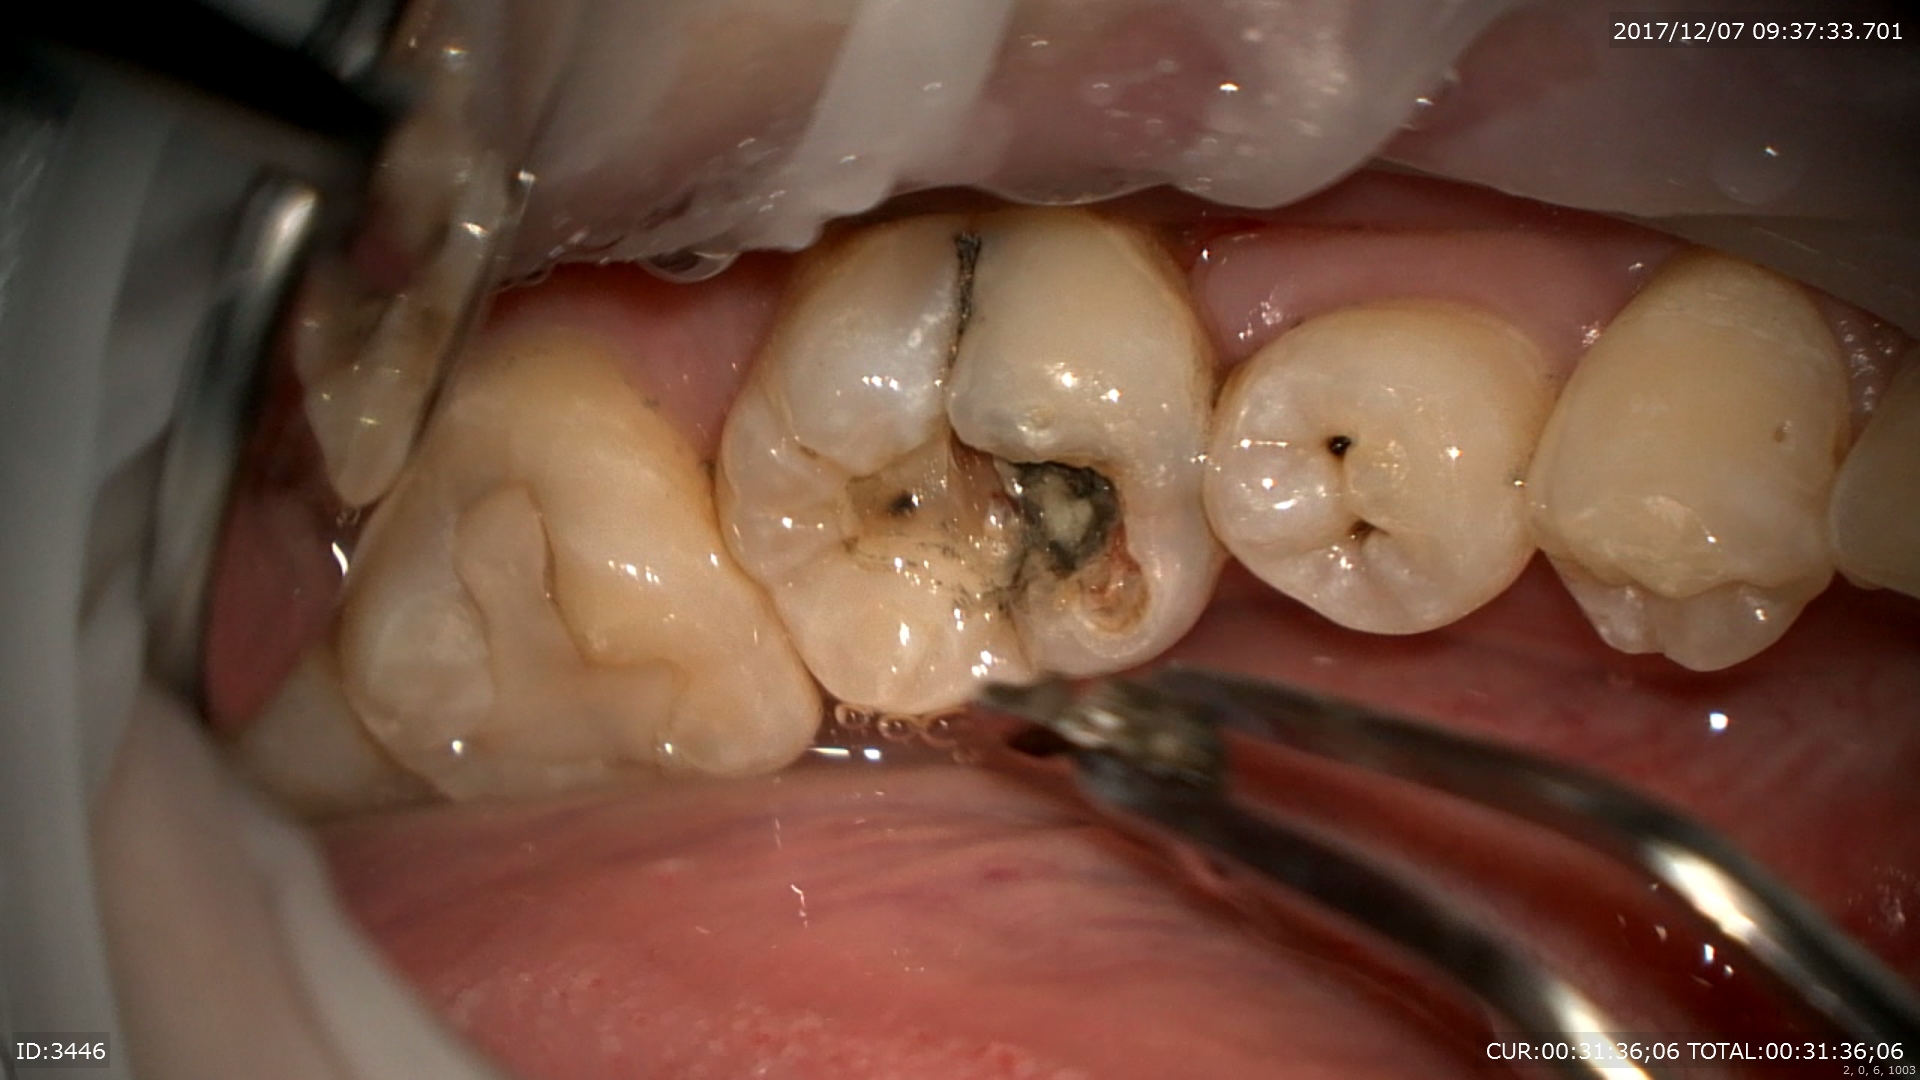

怖いのはここから。この虫歯を追従すると

ザクザク深いところまで。神経に近い。

隣の歯まで転移しています。

ほら隣の歯も。マイクロスコープですからここまで見えます。

神経に近い部分は後遺症が残るのでMTAセメントで覆い

二重で壁を作成